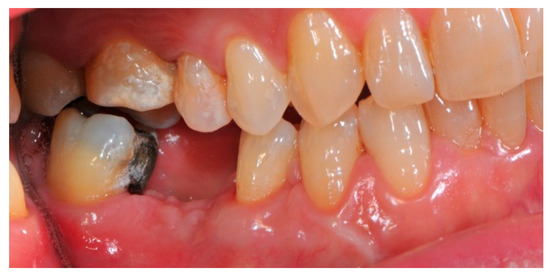

- Flap design: Soft tissue management should be as accurate as possible. The design of the flap should ensure a tension-free primary closure of the wound even after voluminous grafting of the defect. One option (preferred especially in wide vertical defects) is the execution of the so-called “poncho” flap. This technique includes a high vestibular incision of the mucosa, muscle and periosteum in order to undermine the preparation of the flap and to achieve its mobilization, followed by a deep incision in the buccal area with two additional vertical incisions that are performed at an appropriate distance from the occlusal area and the site of augmentation. After the incision, the preparation of a muco-periosteal flap and the remotion of scar tissue, a full thickness flap is raised until the bone defect is uncovered [17,18,19,20]. Finally, the positioning of the customized titanium mesh is passively tested to evaluate its fit intra-operatively (Figure 2, Figure 3, Figure 4 and Figure 5).